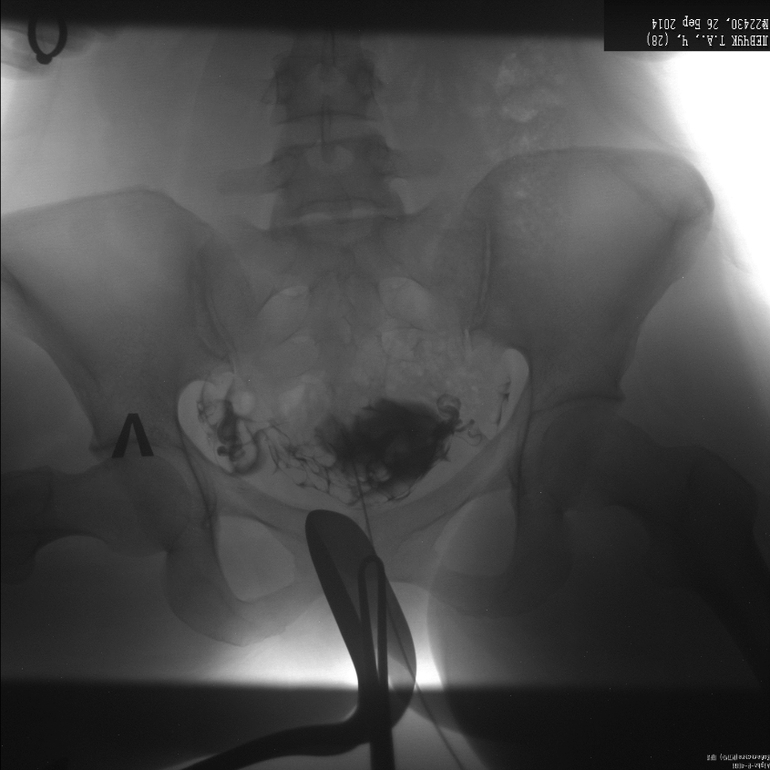

Метросальпингография, посмотрите, неужели все так плохо?

заключения нет, просто сказали, что правая проходима, а левая нет, и трубы тонкие, длинные и закрученные, на лапару отправляют!